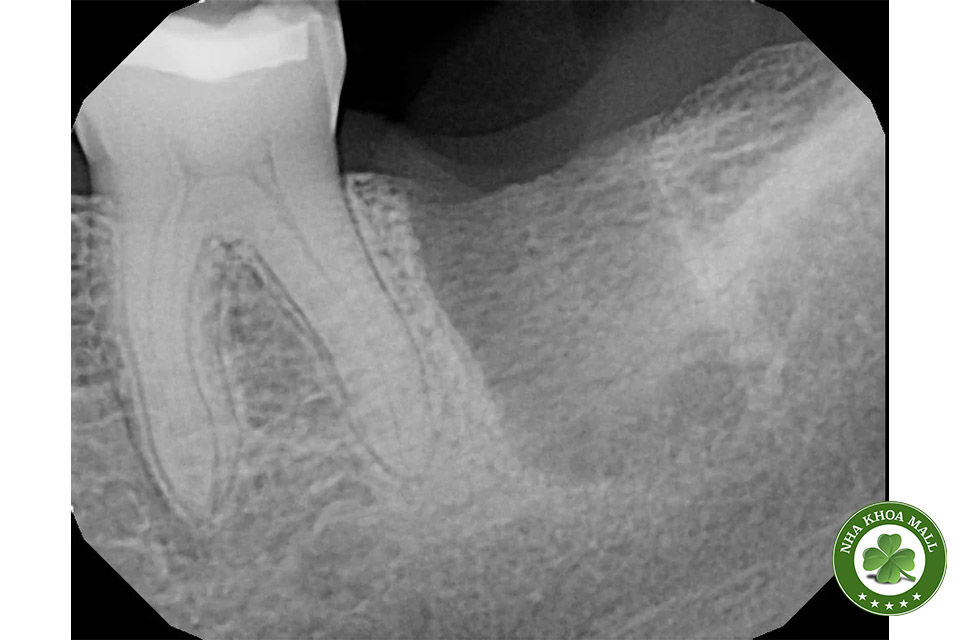

Chỉ khâu là loại chỉ dùng để nối liền các mô mềm trong khoang miệng sau khi thực hiện các thủ thuật nha khoa như nhổ răng, cấy ghép implant hay phẫu thuật nướu. Chúng có vai trò quan trọng trong việc giữ các mô ổn định, ngăn ngừa chảy máu và giúp vết thương nhanh chóng liền lại. Vậy, chỉ khâu lợi có tự tiêu không? Câu trả lời phụ thuộc vào loại chỉ được sử dụng.

- Nhổ răng khôn: Sử dụng để giúp vùng mô lành mà không cần phải quay lại phòng khám để cắt chỉ.

- Phẫu thuật nướu: Hỗ trợ quá trình lành thương tự nhiên mà không gây khó chịu cho bệnh nhân.

- Cấy ghép Implant: Đảm bảo vùng phẫu thuật ổn định mà không cần can thiệp thêm.